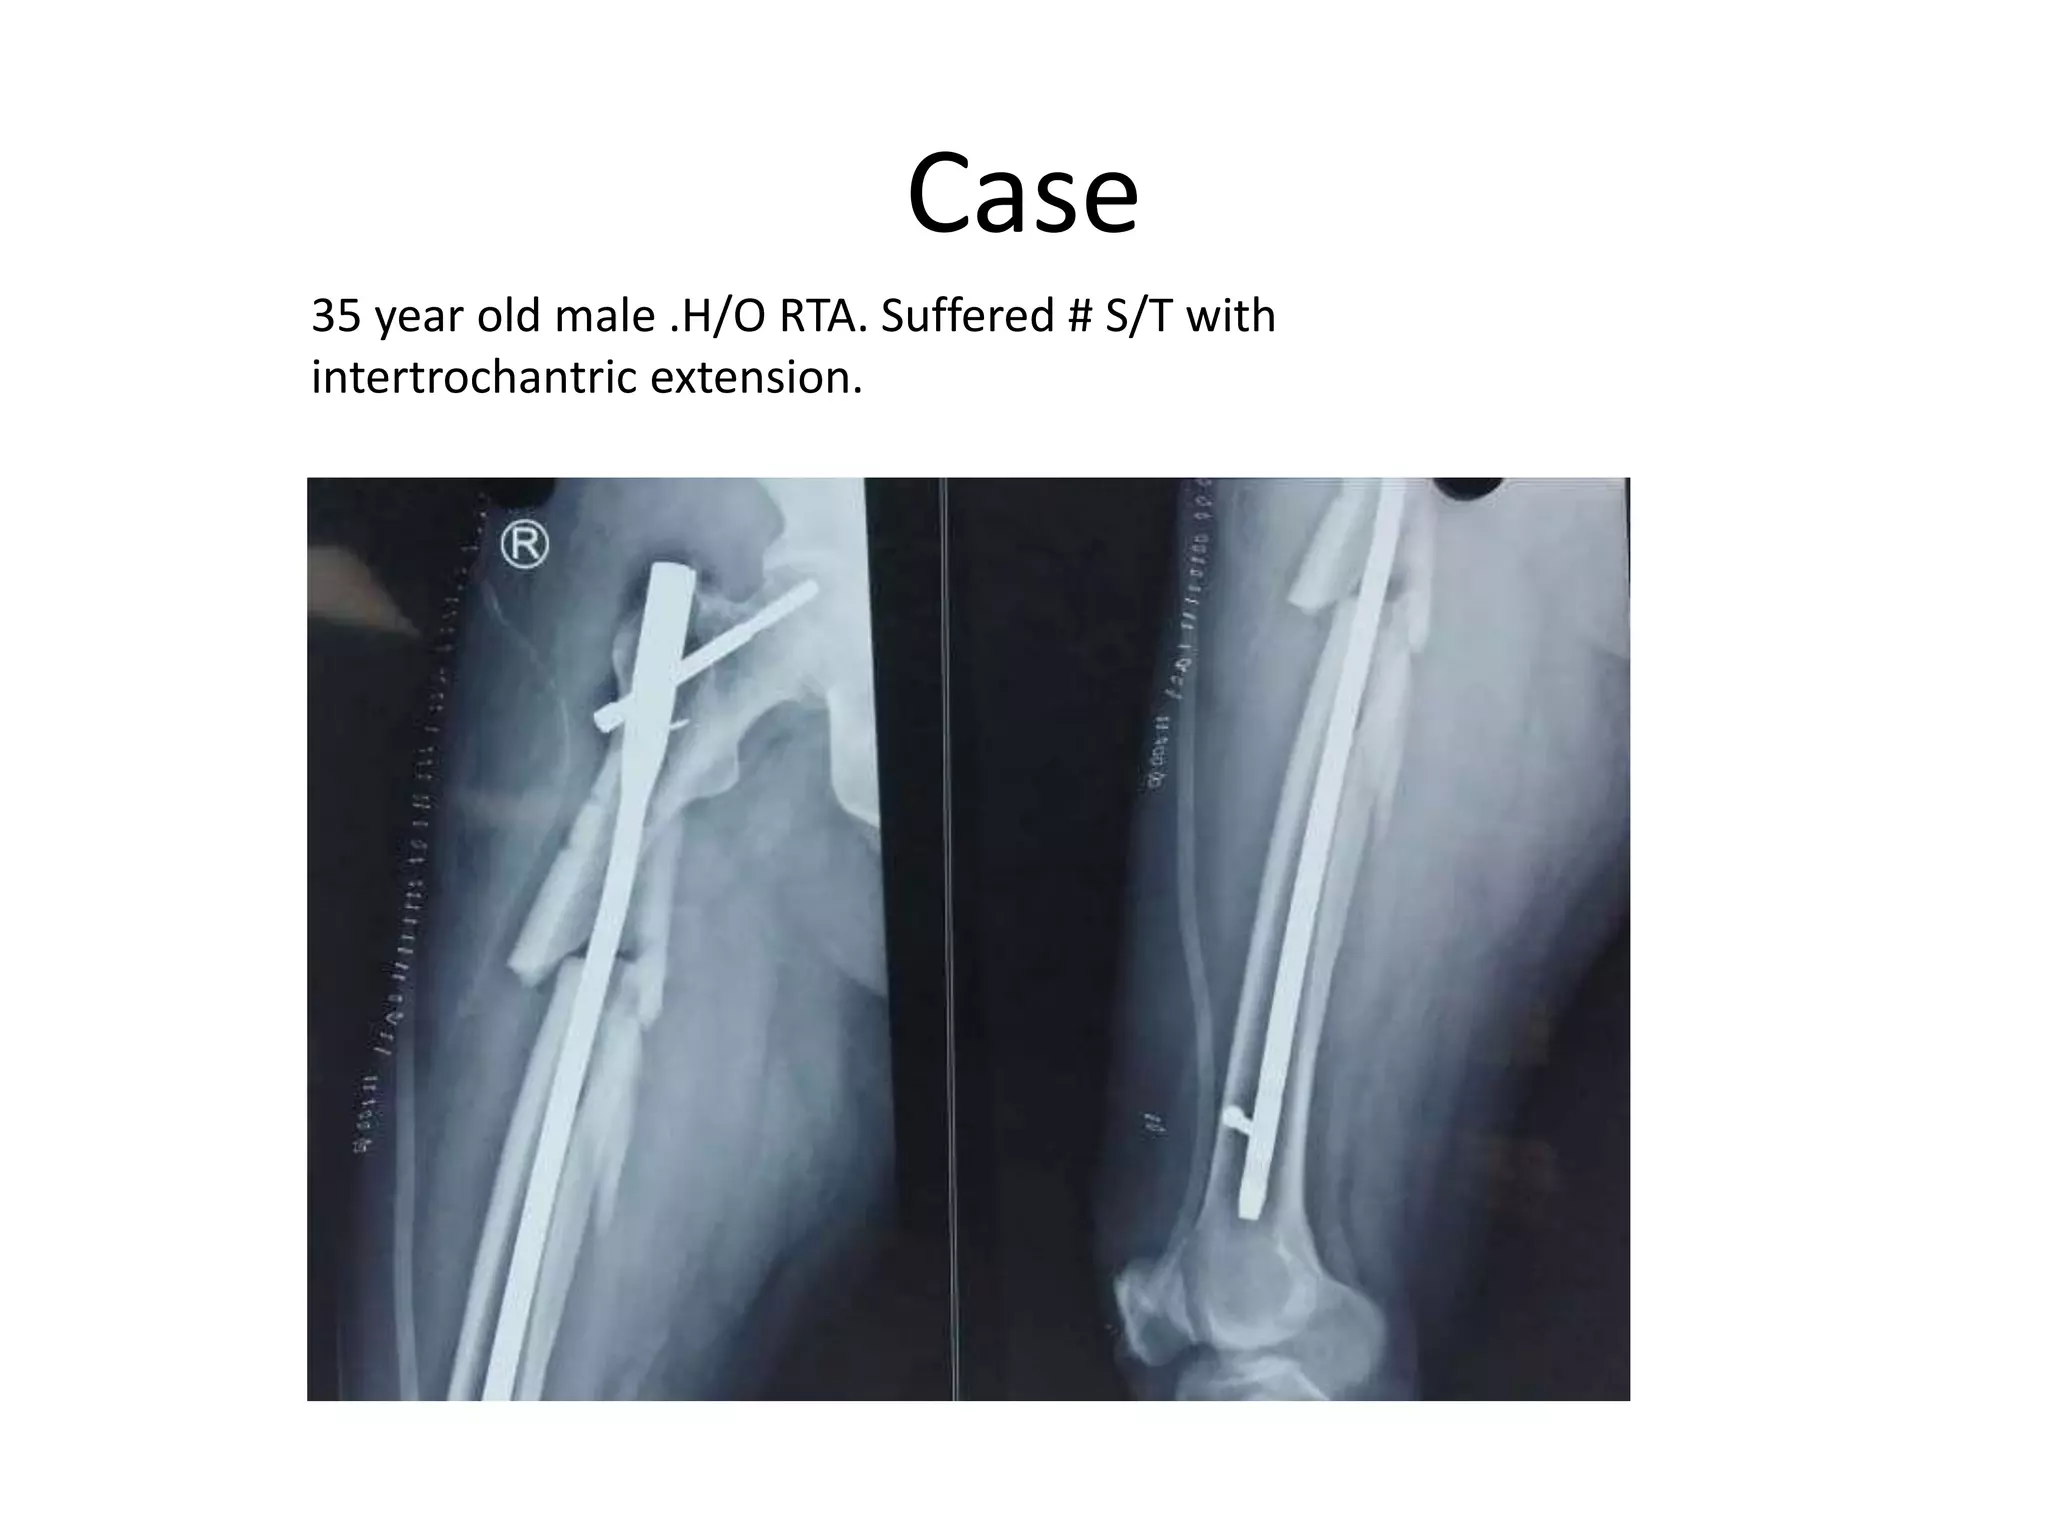

35 year old male .H/O RTA. Suffered # S/T with

intertrochantric extension.

Case 35 year oldmale .H/O RTA. Suffered # S/T with intertrochantric extension.